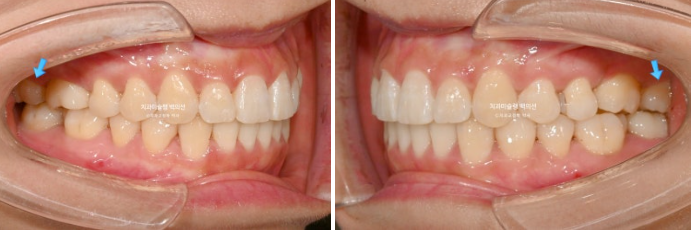

파란화살표 둘째 큰어금니 (제2대구치)자리에 있는 치아는 사실 사랑니입니다.

그 앞 제 1대구치 자리에 와있는 치아는 사실은 제 2대구치입니다.

이제 전후비교 보겠습니다.

총 치료기간은 1년 10개월, 재제작은 2회 했습니다.

23.10~25.08

발치된 큰어금니 자리를 뒤에있는 제2대구치와 사랑니로 감쪽같이 대체되었습니다.